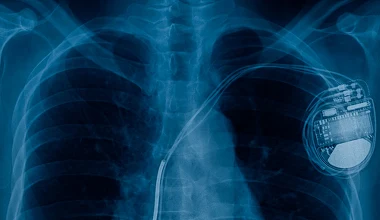

Dziecko Córka Doroty Szelągowskiej ma chore serce. Wrodzone wady serca są coraz częściej diagnozowane